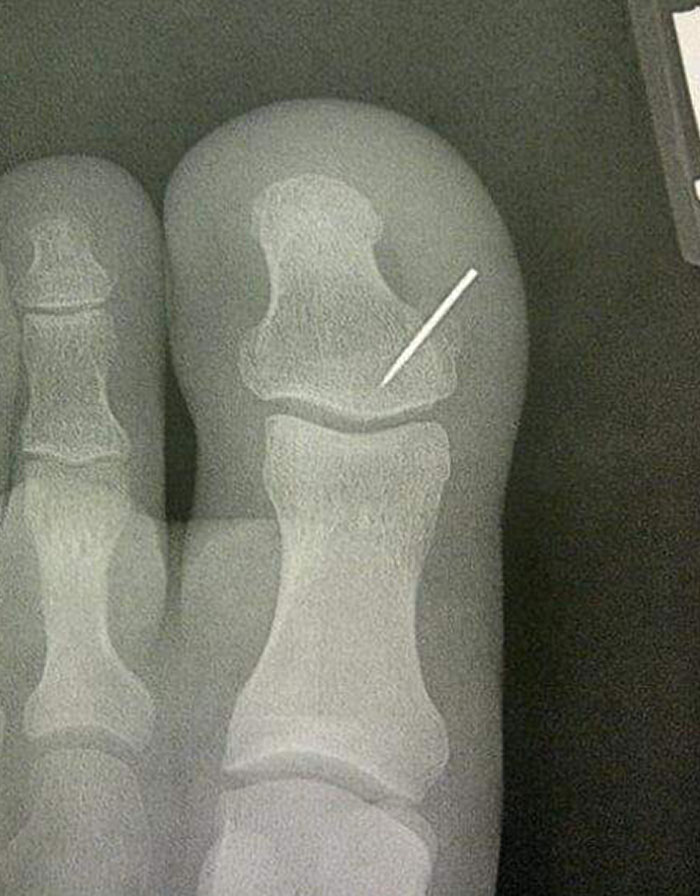

9. Сопругата изгуби игла за шиење на тепихот и ја најдов неколку дена подоцна.